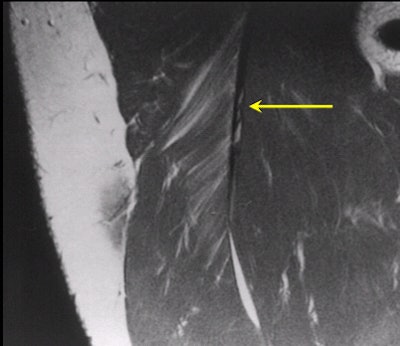

| Hyperintensity of the proximal portion of the long head of biceps femoris muscle is compatible with a strain (arrow). |